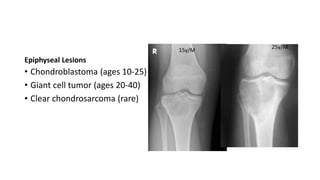

Epiphyseal Lesions

• Chondroblastoma (ages 10-25)

• Giant cell tumor (ages 20-40)

• Clear chondrosarcoma (rare)

15y/M

25y/M